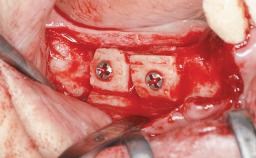

Bone Augmentation Horizontal|Staged

Augmentation Materials Autogenous chips|Autogenous block(s)|Membrane

Bone Volume Deficient horizontally, requiring prior grafting